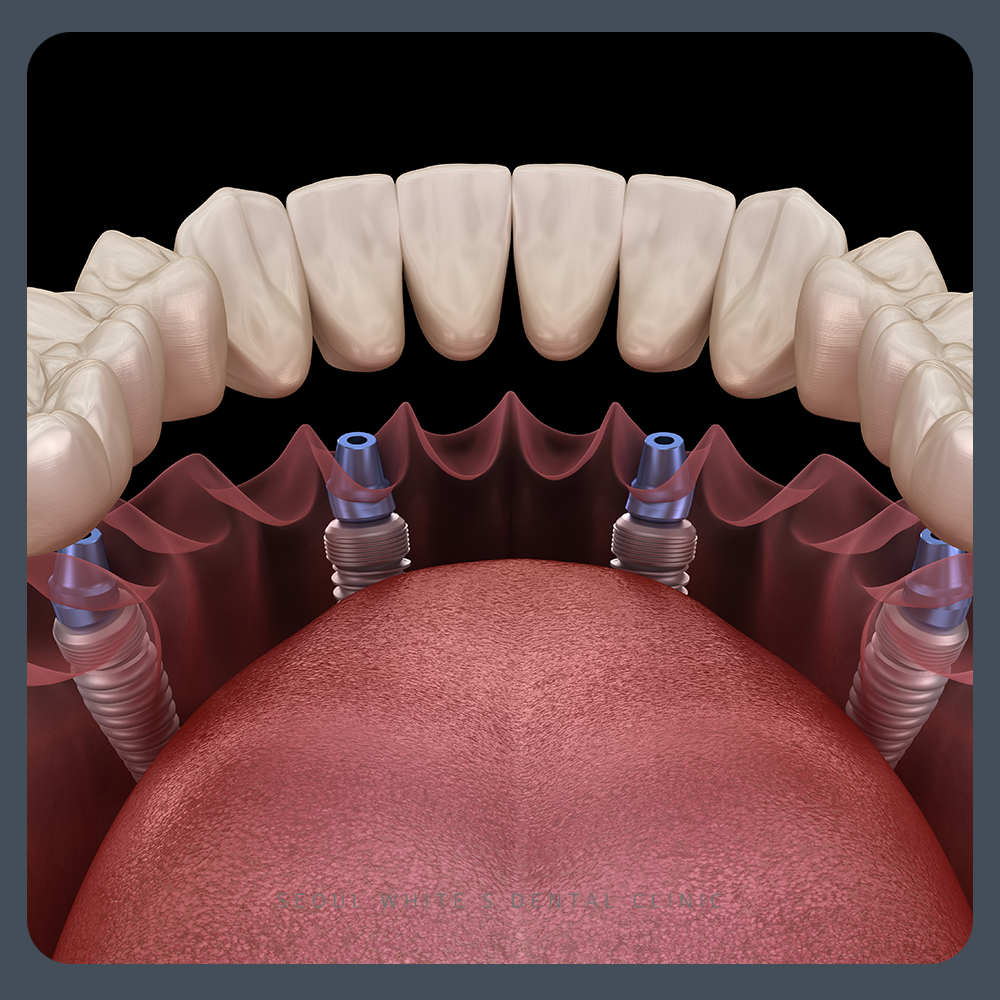

이런 경우, 치주 질환 등으로 인해 발치를 고려하는 상황이 발생할 수 있습니다. 발치 후에는 부분 틀니 또는 임플란트를 고려할 수 있는데요, 오늘은 기존 보철물에 문제가 생겨 발치 후 진행하는 임플란트 식립 치료 과정에 대해 살펴보겠습니다.

보철물이 위치하거나 길이에 따라 부분 틀니를 고려할 수 있습니다. 그러나 상실된 치아 하나를 대체하기 위해 브릿지 형태의 보철물을 사용한 경우, 부분 틀니는 경제적인 부담이나 불편함이 더 클 수 있습니다. 임플란트에 비해 훨씬 더 불편하게 느껴질 수 있죠. 특히 치아 하나에 크라운을 씌운 경우에는 부분 틀니 사용이 더욱 불편하고 비효율적일 수 있습니다. 광복동치과 서울화이트S치과에 내원해주신 환자분의 케이스를 함께 살펴보도록 하겠습니다.